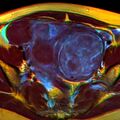

-

A relatively large submucosal leiomyoma; it fills out the major part of the endometrial cavity